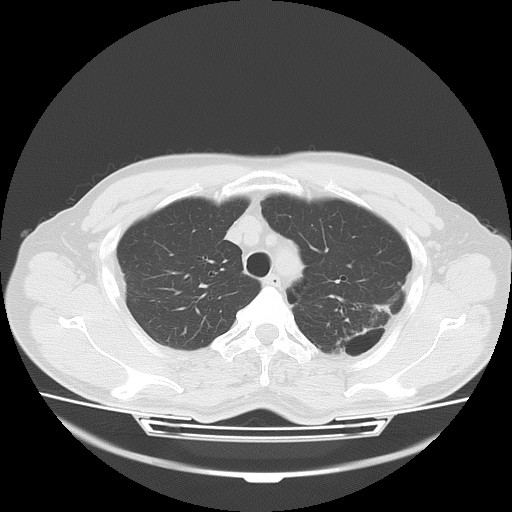

【コンピュータ断層診断装置(Computed Tomography:CT)】高性能16列マルチスライスCTで精密検査が受けられます。

短時間で断層像(輪切り)が鮮明に撮れます。

コンピュータ断層診断装置(Computed Tomography:CT)での撮影画像例。